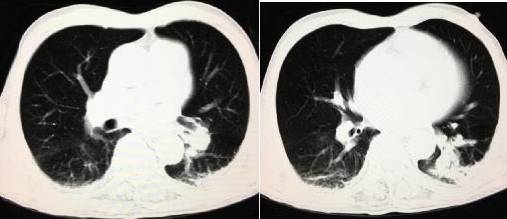

肺窗: 医学百科网 | YxBaike.Com

平扫 CT 示右肺动脉干及下肺动脉分支内高密度影(红箭示)